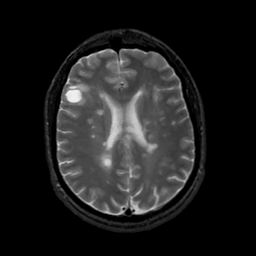

MR Study #7, March 24, 1991 -- Slice #31